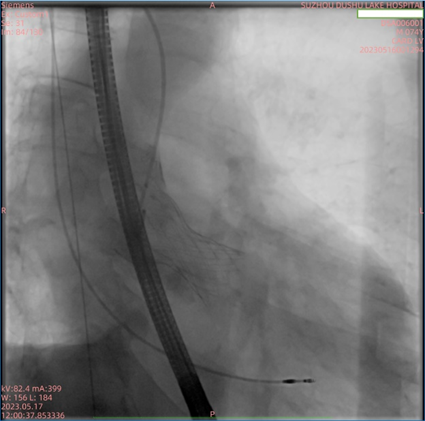

5月17日上午,在多学科协作诊疗(MDT)团队的倾力协助及全体医护人员的共同努力下,苏州市独墅湖医院(苏州大学附属独墅湖医院)心血管内科周亚峰教授团队成功地为一名“Type 0型”主动脉瓣二叶畸形合并重度狭窄患者完成了经导管主动脉瓣置换术(以下简称“TAVR”),手术顺利,术后效果显著。此次手术使用的经导管主动脉瓣膜系统,为前沿独特创新技术,不仅帮助患者解除了困扰多年的病痛,同时也体现了我院心内科在处理复杂病例方面较高的技术水平和丰富的经验,标志着我院在高难度微创心血管介入领域取得突破性进展。

患者为74岁男性,因“反复胸闷1年余,加重1周”入住我院心内科病房。入院后完善心脏彩超,根据结果诊断为主动脉瓣重度狭窄。此次手术选用园区某生物医药公司自研的瓣膜,术前跨瓣压差测得68mmHg左右,术后即刻跨瓣压差小于5mmHg,手术效果较好。